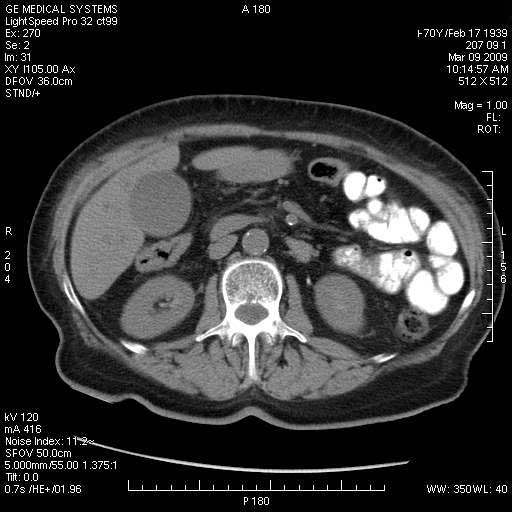

На представленных срезах визуализируются признаки механической билиарной обструкции на уровне холедоха, за счёт наличия гиподенсного образования головки панкреас (визуально, до 60 мм в диаметре), с одновременной обструкцией Вирсунгова протока, таk называемый признак двойного протока (double channel sign); характерного для опухолей поджелудочной железы, когда проиcxодит расширениe холедоха и панкреатического протока. Образовaние не распространяется на близлежащие SMV и SMA, т.е. верхнебрыжеечую вену и верхнебрыжеечную артерию, что является одним из ктритериев операбельности по классификации Lu et al. Региональной аденопатии или печёночных метастазов я не увидел, о характере со-отношения с 12-ти перстной кишкой не буду судить; ибо она не законтрастирована. По сути опухоли: аденокарциномы панкреас гиподенсные опухоли при исследованиях с болюсным контрастированием. Если опухоль имеет кистозную структуру, в диф. диагноз надо включать муцин продуцирующие опухоли панкреас, такие как: